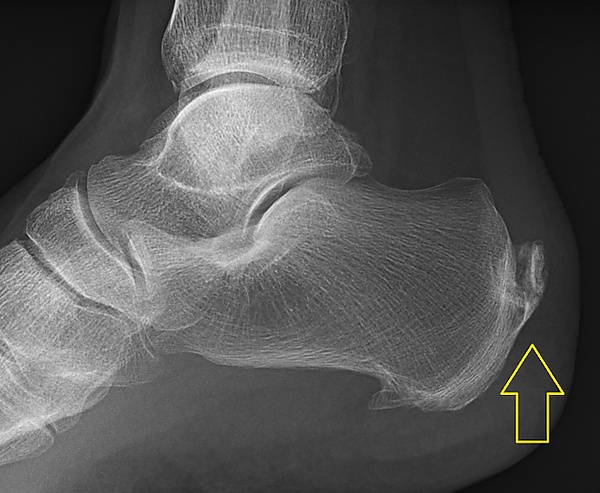

Тендинит ахиллова сухожилия обычно диагностируется на основании анамнеза и физикального осмотра сухожилия. Проекционная рентгенография показывает отложения кальция в сухожилии в месте его прикрепления к пяточной кости примерно в 60 процентах случаев. При помощи магнитно-резонансной томографии (МРТ) можно определить степень дегенерации сухожилий и выявить дифференциальные диагнозы, такие как бурсит[4].

• Боковая и аксиальная рентгенограммы пяточной кости: эти исследования визуализации могут выявить кальцификаты в проксимальном расширении прикрепления сухожилия или костные выступы в верхней части пяточной кости. Кроме того, рентгенограммы полезны для исключения патологических опухолей костей[22].